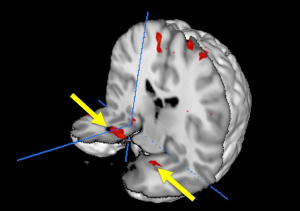

當回憶創傷性事件時,前顳葉區域(如圖所示),包括杏仁核和海馬體會激活。實驗過程

八名乘客分別都躺在磁共振成像(MRI)掃瞄器里,在觀看這些視頻剪輯時回憶他們乘坐越洋航空236號班機時的細節體驗。他們的記憶與涉及情緒記憶的大腦區域網路里增強的回應密切相關。與回憶中性事件相比,回憶創傷性事件時增強的大腦區域包括杏仁核、海馬體、中線前額和後部區域。